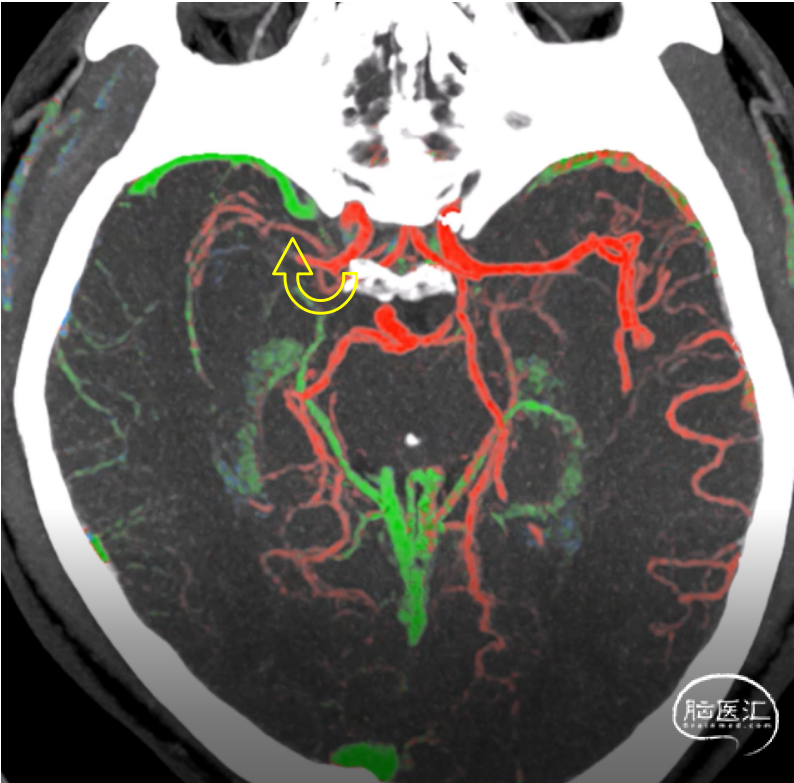

CTA

患者存在着315cm3的缺血半暗带区域,有开通血管的必要性,与患者母亲沟通后,同意了接下来的血管内治疗。

1、青年卒中,醒后进展,时间窗远超24h,影像检查:右侧大脑中动脉供血区平均通过时间(MTT)、达峰时间(TPP)延长,脑血流量(CBF)减少,脑血容量(CBV)正常,考虑脑梗死前期。患者存在着315ml的缺血半暗带区域。显示仍存在可挽救的脑组织,有取栓治疗获益的可能性。

MR CLEAN LATE最新结果显示,在发病6-24h的晚窗患者中,根据CTA上的侧枝循环是否存在来选择患者进行血管内治疗,能显著使患者受益。本例患者的侧支循环来自于CTA上提示的副大脑中动脉。

术前右侧颈内动脉造影示右侧副大脑中动脉